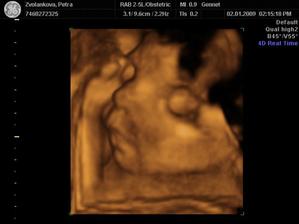

Tak jsme po UTZ,miminko se mlelo a krásně hýbalo,vše bylo vidět,vše je v pořádku a hlavně

JE TO KLUK....TAKŽE BUDEME MÍT MATYÁŠKA🙂))))))